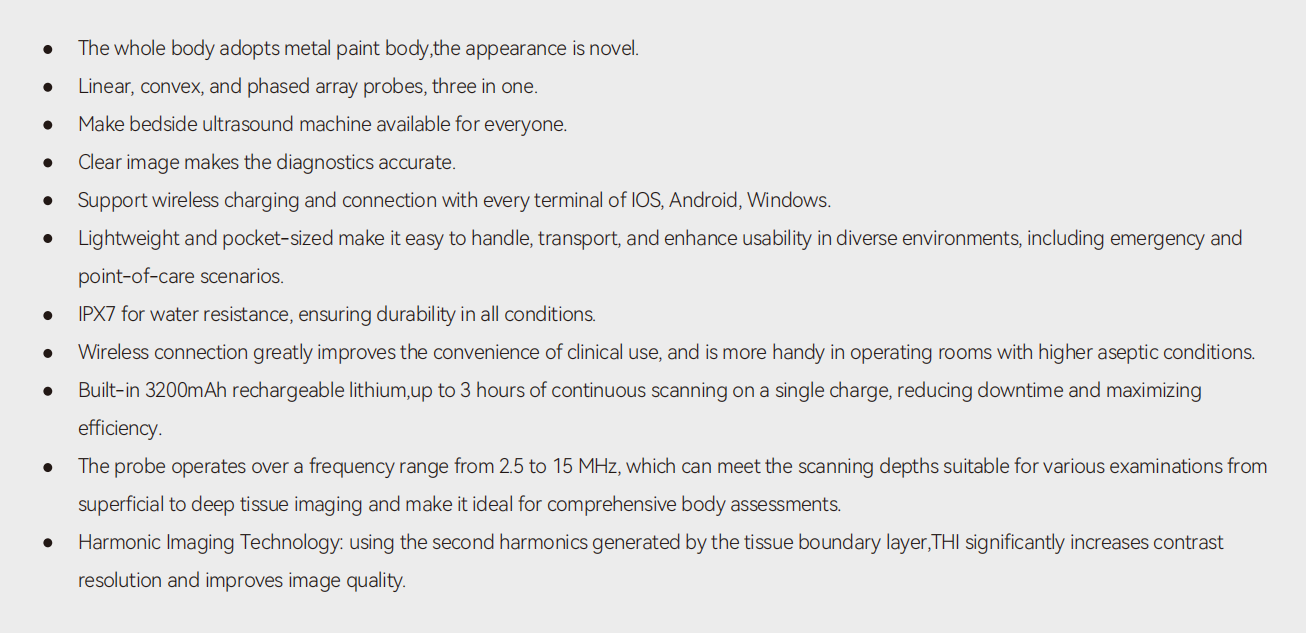

Carotid + CF + PW + Auto Trace

Carotid + CF + PW + Auto Trace